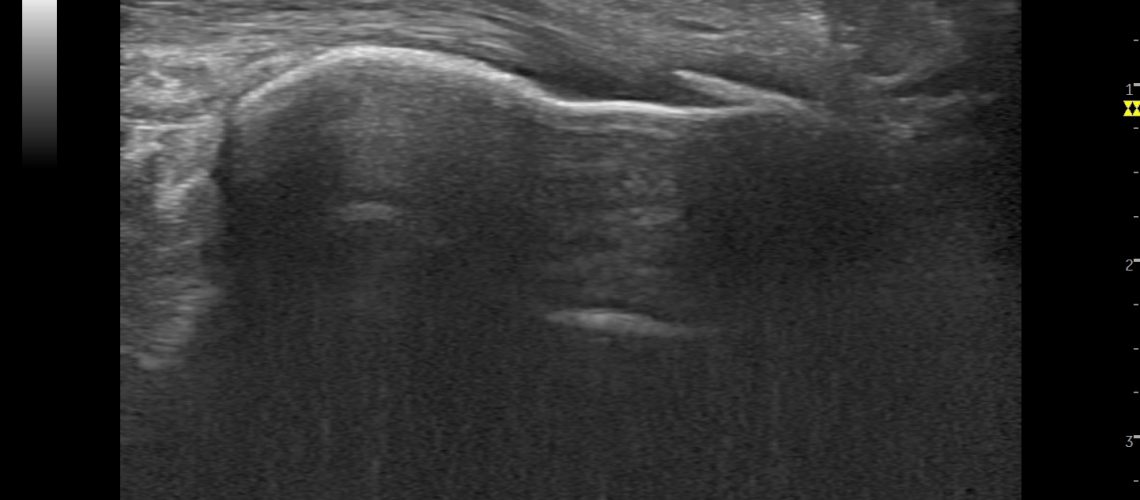

A través de su pantalla podemos ver los tejidos blandos del cuerpo: músculos, tendones, ligamentos y superficies óseas.

Y es que la imagen que transmite, nos permite entender e interpretar las dolencias del paciente y realizar un seguimiento de las lesiones de una manera más eficaz, rápida y personalizada.